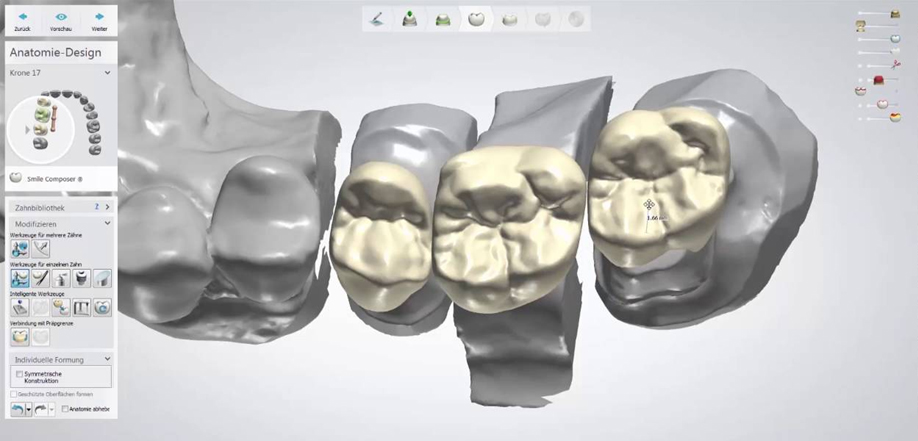

Der Zahnersatz wird in Aachen lokalisiertem Labor fertiggestellt. Das Labor verfügt über umfangreiche Erfahrung bei der Ausführung von zahnärztlichen Arbeiten sowohl in Keramik als auch in Metall: Inlay, Onlay, Overlay, Veneers, Kronen, Teilkronen aus allen Vollkeramikmaterialien und Hybriden und Zirkonium. Es wird insbesondere Folgendes ausgeführt:

• Vollkeramikbrücken – Brücken und Unterbauten aus Zirkoniumdioxid

• Implantat-Prothetik, Individualverbinder, Kronen und anschraubare Brücken und Zementbrücken